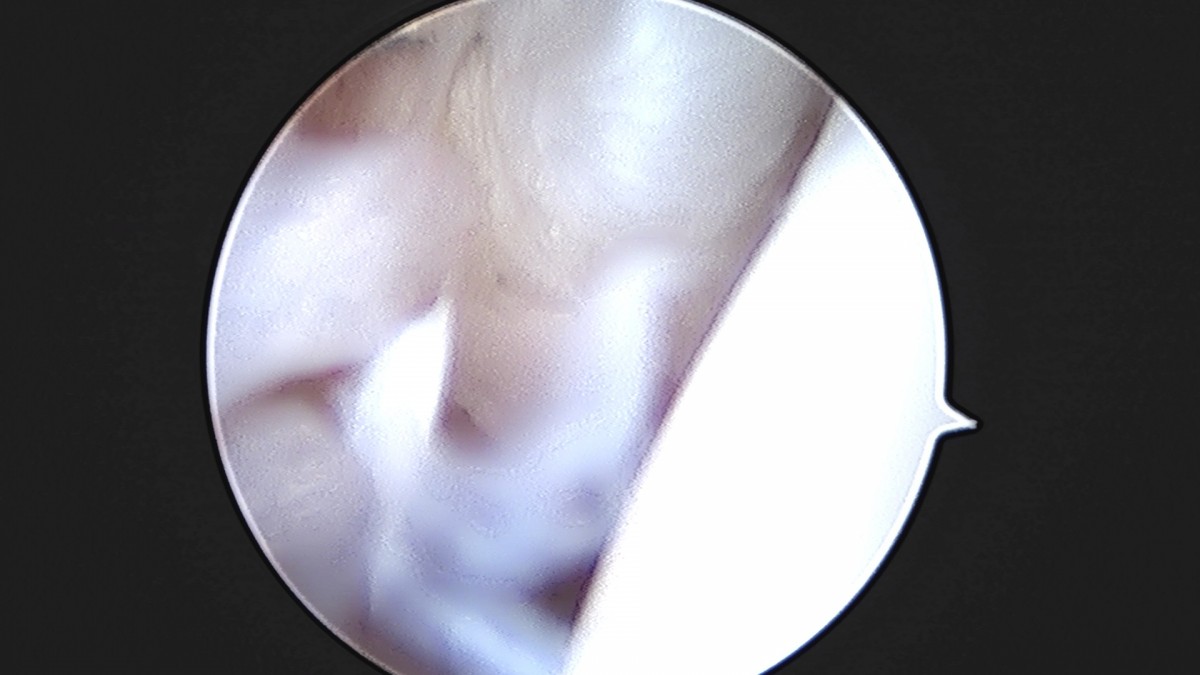

이재상원장님 발목 인대 봉합술 이지O 환자

작성자 최고관리자 댓글 0건 조회 681회 작성일 25-09-16 16:26